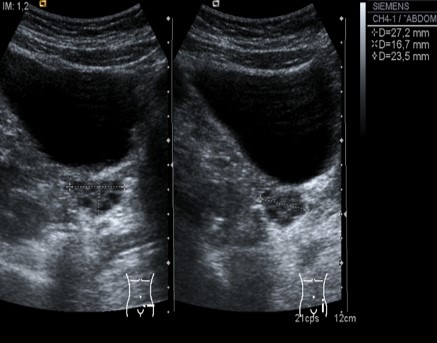

Mioma. Medidas.

Útero miomatoso. Aspecto heterogéneo.

Los miomas típicos son masas sólidas hipoecogénicas en el espesor del miometrio. Hay gran variedad en cuanto a ecogenicidad, tamaño, número y localización de miomas.